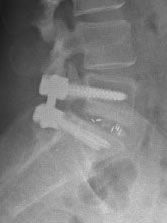

Le but de la chirurgie lombaire est de décomprimer les racines nerveuses lombaires. Parfois, surtout en cas de « spondylolisthésis » le geste de décompression doit s’associer à une stabilisation du segement impliqué avec des vis pédiculaires et une cage intersomatique, cette intervention s’appel une fusion lombaire.

- stabilisation mono ou pluri-segmentaire